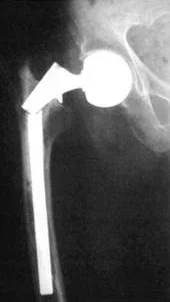

Вывих эндопротеза

Т.к. искусственный сустав не является полноценной заменой суставу настоящему, то его функциональные возможности, соответственно, ниже. При некоторых неосторожных движениях в суставе может произойти вывих эндопротеза. Как и при вывихах в натуральных суставах, считается, что вывихивается дистальный компонент протеза по отношению к проксимальному (например, в тазобедренном эндопротезе вывихивается головка эндопротеза).

При произошедшем вывихе, его вправляют под наркозом. После этого ногу иммобилизируют. По окончании острого периода всегда сохраняется риск повторных вывихов. Если закрытым путём не удаётся вправить вывих, делают операцию открытого вправления вывиха.